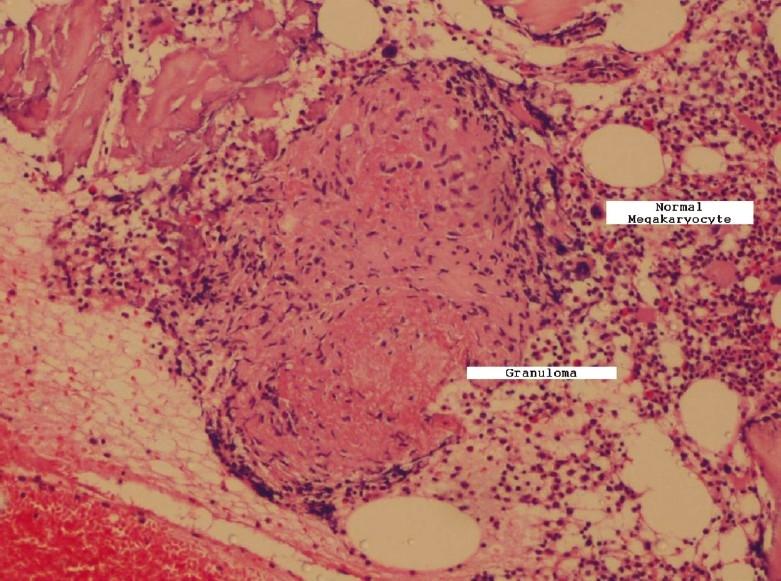

Tuberculosis has a variety of hematological manifestations. Immune thrombocytopenic purpura is an uncommon manifestation of tuberculosis. We present a case of disseminated tuberculosis with isolated thrombocytopenia. While TB granulomas in the bone marrow can themselves cause hematological abnormalities, persistent thrombocytopenia refractory to anti-TB therapy may be ITP associated with TB.

https://cdn.ncbi.nlm.nih.gov/pmc/blobs/c26f/3276039/dae13bf8e097/LI-29-63-g001.jpg